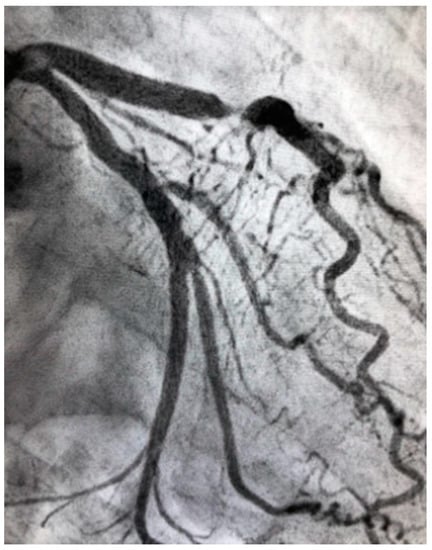

Figure 1.

Intravascular ultrasound demonstrating coronary artery stenosis most likely due to plaque erosion.